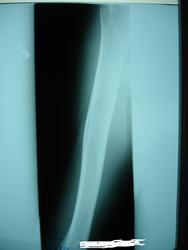

Здравствуйте, уважаемые коллеги прокомментируйте пожалуйста снимки(что это может быть?) 46 лет, муж., появилась болезненность при движении рукой (3 недели назад) и мягкотканный валик по боковой поверхности правой плечевой кости, травму отрицает.

"Мягкотканный валик" может быть сокращенной мышцей вследствие разрыва сухожилия. В кости патологии нет, но может наслаиваться тень гематомы.

На мой взгляд, бугристость как бугристость.

На третьем снимке цепляет  неровность контура, все-таки порекомендовала бы контроль недели через 2-3

Болезненность локализуется на уровне кортикального просветления, травмы не было, кожа не изменена.

Периостальной реакции я не вижу, контур ровный.

уместно ли здесь говорить о "злом" процессе.

Возможно оссифицирующий миозит

Оссифицирующий миозит всё же больше выглядит так:  http://www.radiomed.ru/blogs/andrei-kastarnov/ossifitsiruyushchii-miozit

Что за полоска просветления линейной формы в кортикальном слое плечевой кости?

Надо думать, что "это" норма.

Ну вот, справа в кортикальном слое бегристости плечевой кости полоска просветления есть, а слева - нету. Так , может, справа "не норма"?. Или за счёи проекционного искажения такая разница?

видимо не "докрутили" руку

контроль кортикального расслоения